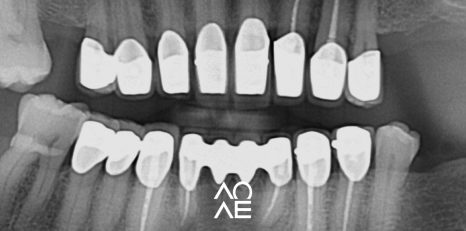

방사선 검사 등을 꼼꼼하게 진행해보니

교정이 아닌 크라운으로 치료가 가능한

구강 상태를 가지고 계셨기에 크라운 치료를

결정하고 진행하게 되었습니다.

| 치료 전(23. 12. 03) | 치료 후(24.06. 20) |